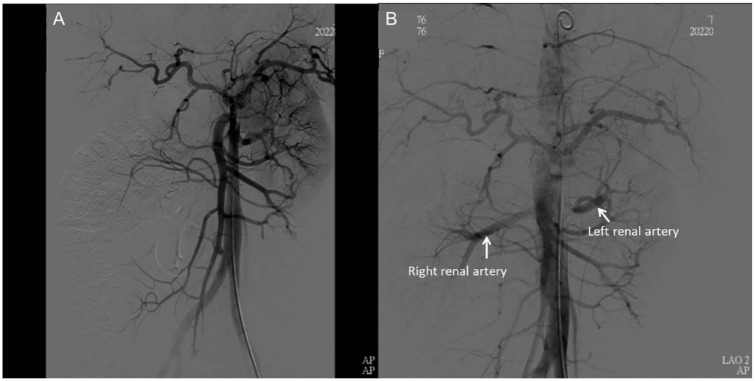

Case report: A case report involving a 33-year-old female with Stanford type B aortic dissection at 32 + 3 weeks gestational age highlights the importance of being alert to the symptoms and signs of this condition, particularly in patients with hypertension or a history of connective tissue disorders. The case report suggests a delivery first strategy followed by TEVAR procedure as the preferred approach for managing aortic dissection in pregnancy. This approach can alleviate pressure on the aorta, reduce the risk of rupture, and provide time for stabilization and preparation for the TEVAR procedure.